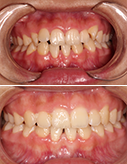

18岁少女矫正结束,一切刚刚好

少女牙齿整齐,笑容更显可爱